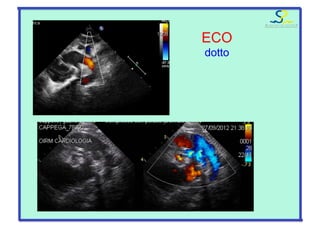

ECO

“4” camere: ipo VD/VS

ipoVS